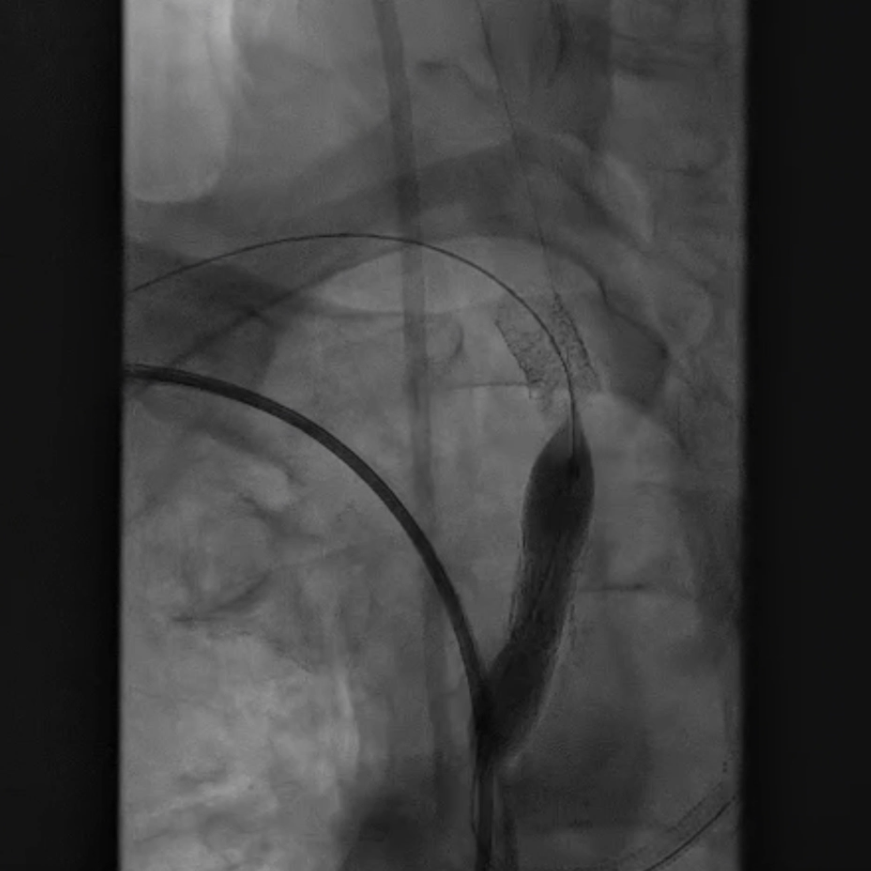

脑保护措施:更换加硬导丝后,采用Filterwire保护伞及0.018导丝选入右颈总动脉,进一步送入右颈内动脉释放保护伞。

跟进长鞘至无名动脉起始

Filterwire 3.5-5.5 保护伞

导丝选入右颈总动脉内

导丝选入右颈内动脉

放置保护伞